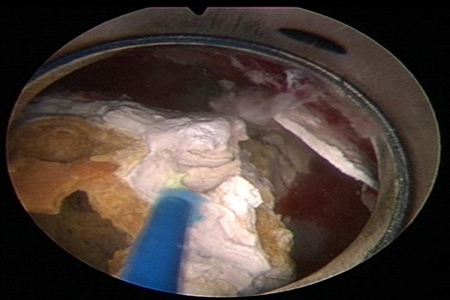

激光碎石是高能高效的一种,可以把比较大的结石打成小块,甚至现在有更高的激光可以完全做到粉末化,打成非常小的结石后,有利于患者的排出,激光有着各种各样的优点,在临床上应用的也越来越多。